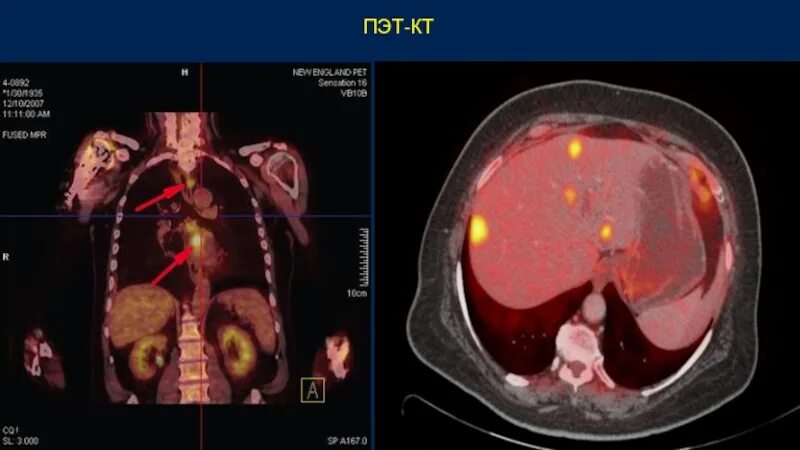

Метастазы после химиотерапии